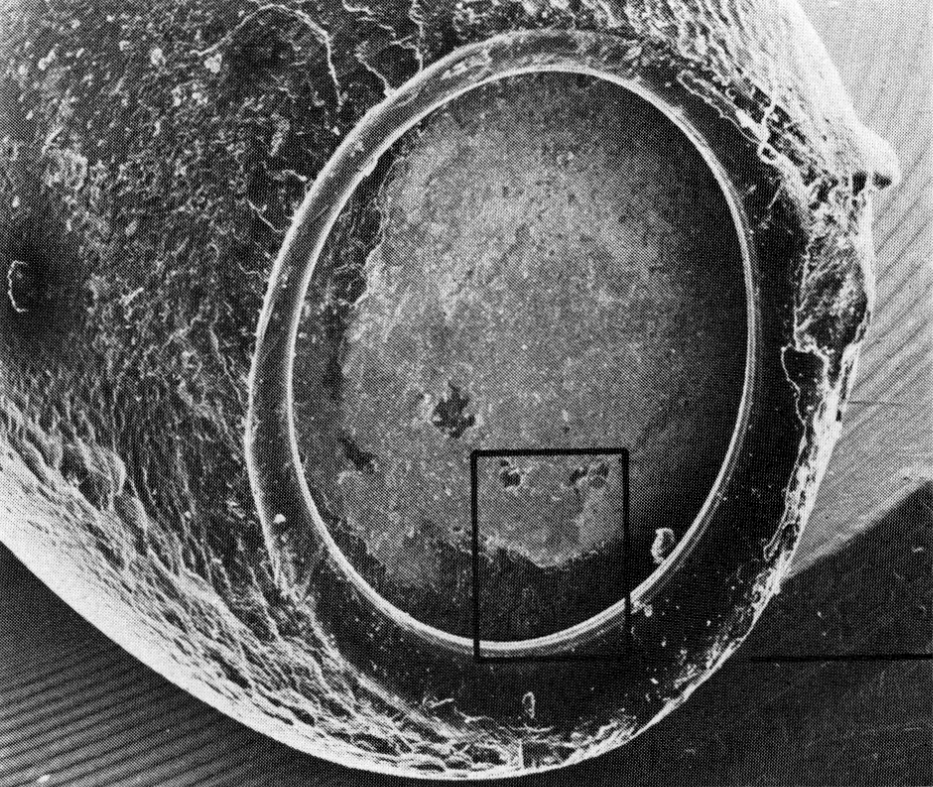

— Гликокаликс способен на всё! Срочно присылай мне эти бутылки, — восторженно прокричал Билл в телефонную трубку. — У нас как раз появился новый сканирующий электронный микроскоп (СЭМ). Теперь мы можем изучать прикреплённые бактерии, не отрывая их от поверхности. Таких фотографий ты ещё не видел!

Мерри прислал Костертону сразу десять бутылок с хлоргексидином. Билл отрезал от каждой небольшой кусочек пластика и после подготовительных процедур фиксации, металлизации[12] и сушки засунул их в СЭМ. Как и предполагалось, почти все бутылки изнутри были покрыты толстым слоем гликокаликса, из глубин которого на исследователей взирала довольная жизнью Serratia marcescens. В результате лабораторных испытаний выяснилось, что укрытая полисахаридным матом серрация выдерживала концентрации хлоргексидина, доходившие до 20 мг/мл, и могла выживать в бутылке с антисептиком на протяжении многих лет.